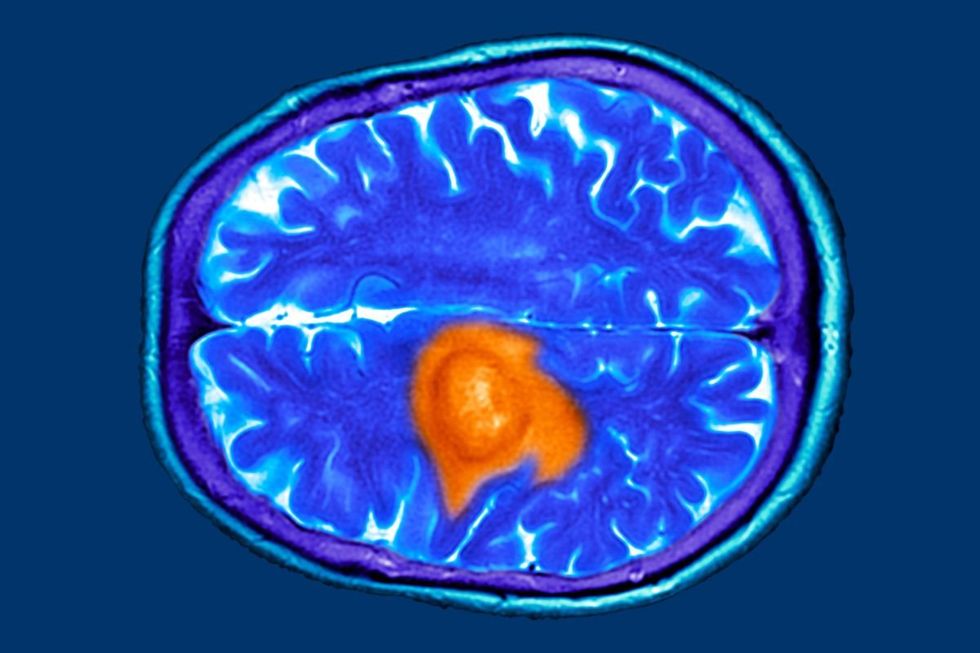

Tau protein deposits in the brain are closely associated with dementia, making these findings particularly noteworthy for those concerned about cognitive decline in later life.

Tau protein deposits in the brain are closely associated with dementia

Following this initial measurement, the subjects underwent PET brain imaging approximately 16 years later to evaluate levels of both tau and amyloid beta proteins.